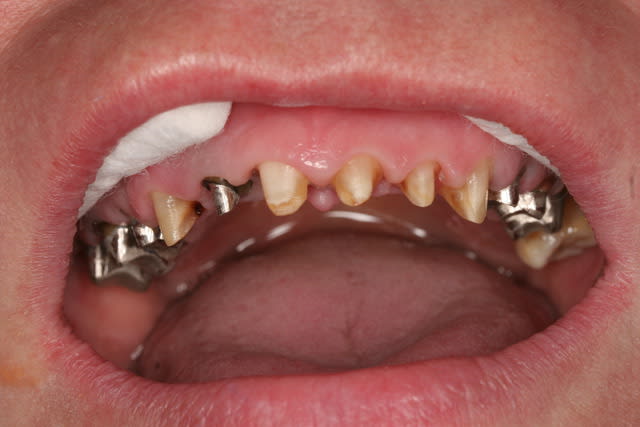

Récemment Céramik râlé, parce qu'il n'y avait pas de nouveau cas (esthétique je crois) à se mettre sous la dent. Je me jettes à l'eau avec ce dernier cas posé ce vendredi (y'a pas plus frais), une larme à l'oeil parce qu'il s'agit aussi du dernier gros cas dans mon cabinet que je quitte cette semaine pour rejoindre ma belle et nos p'tits bouts loin la bas dans le sud.

La patiente a un sourire très médiocre avec migration de plus en plus marqué du bloc incisivocanin sup. Comment l'aidez vous?